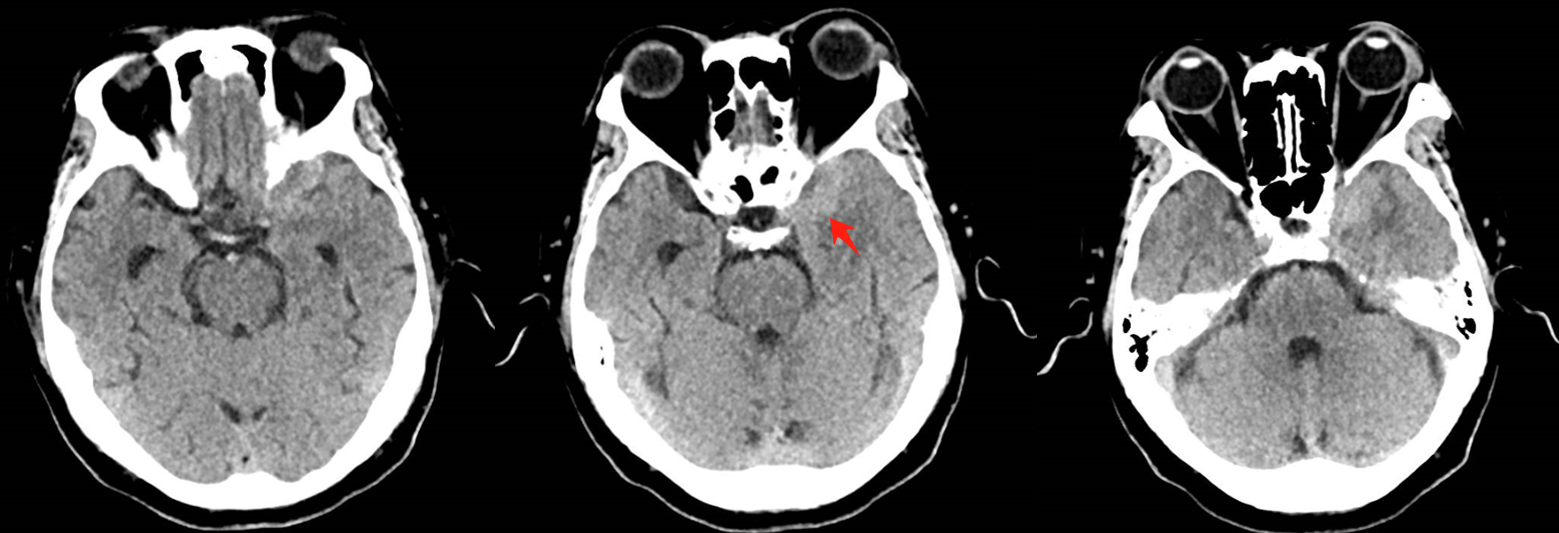

该患者入院后完善常规颅脑影像学检查,左侧颞叶病变,疾病性质不详,转移瘤、胶质瘤、炎症类疾病均不能排除,遂行PET-CT检查,提示左侧颞叶高代谢,淋巴瘤不能排除。组织MDT会诊建议可先行腰椎穿刺查脑脊液脱落细胞学、感染指标,若仍不能确诊,可进一步行开颅病灶切除,术中快速冰冻,根据冰冻结果决定手术手术策略。患者脑脊液脱落细胞学结果:较多淋巴细胞,少许单核细胞及个别中性粒细胞,未见异形细胞,脑脊液常规、生化、脑脊液培养未见细菌生长,诊断仍不能明确,且患者病情进展迅速,患者神志呈昏睡状态,颅脑MRI提示病变较前明显增大(影像学检查间隔两周),且水肿明显加重,遂行开颅病变切除术。术中见部分病变累及蝶骨嵴硬膜,病变质地硬韧,内有多个囊腔,囊内容物为黄色粘稠样脓性物质,留取囊液及实性部分送快速冰冻,在等待冰冻过程中,进一步探查见肿瘤侵犯左侧颞叶,该部位肿瘤质地相对软,无包膜,与周围脑组织无边界,血运不丰富,内有多个囊腔,且肿瘤侵犯侧裂池、颈动脉池,左侧视神经、颈内动脉、大脑中动脉均被病变包绕,且该处肿瘤质地偏硬韧。术中快速冰冻提示组织大片变性坏死,伴胶质增生及淋巴增生。结合病变质地及冰冻结果,考虑为非肿瘤性疾病,可能为炎性病变伴肉芽肿形成可能性大,且肿瘤质地硬韧,累及范围广泛,难以全切,遂行肿瘤大部分切除后结束手术。术后病理结果明确后予以伏立康唑、醋酸卡泊芬净抗真菌治疗。在治疗过程中患者先后出现脑出血、脑梗塞,最终因治疗周期长,花费高、效果不确定等因素,家属放弃治疗,于术后1月去世。

GM实验,GM是曲霉菌细胞壁的主要成分,是疾病早期释放至体液中的抗原之一。据报道,脑脊液GM试验诊断ICA的敏感度及特异度分别为88.2%及96.3%,且阳性预测值及阴性预测值均超过90%,脑脊液GM水平与曲霉菌感染严重程度相关,监测该指标可评价治疗效果及预后。影像学检查具有多样性,多为反复慢性炎症、肉芽肿样改变,部分易累及颅底。

目前确诊ICA仍依赖于病灶切除或活检,获得组织病理学、直接镜检或培养证据。《颅内曲霉菌病诊治中国专家共识》推荐:当临床症状怀疑ICA时,应尽早行脑脊液检查(常规、生化、培养、G试验、GM试验及mNGS)及颅脑MRI平扫+增强检查。怀疑窦源性ICA时,还应加做颅底CT检查。当临床症状符合ICA,但上述检查结果为阴性时,可重复送检。条件允许时,及时行标本镜检与培养获得确切证据。尤其是对于长期应用激素、免疫功能缺陷高危患者。